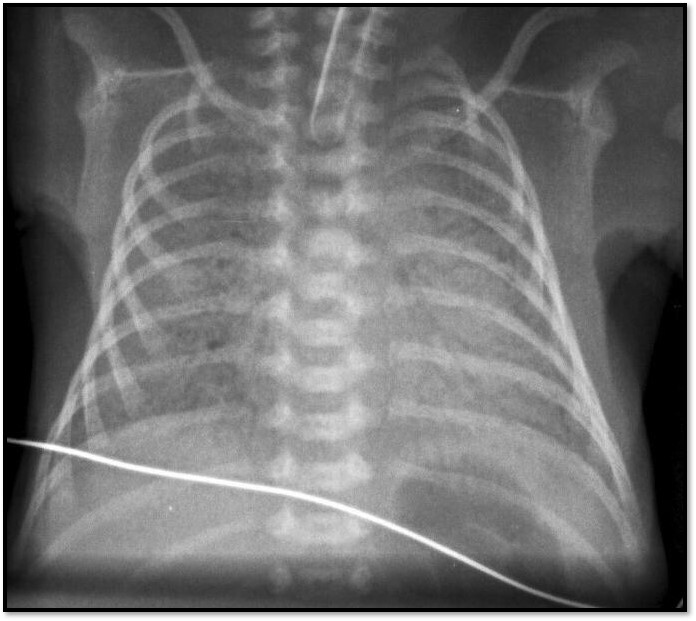

Q

What pathology is seen here? How do we know?

A

-IDRS

-Seeing the darker airways

How well did you know this?